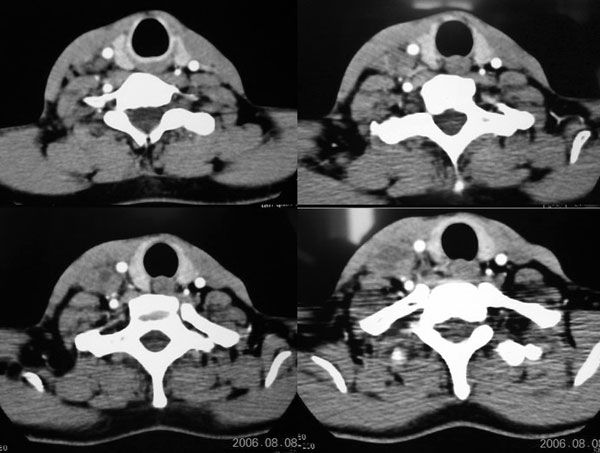

右侧颈部软组织肿块,边界清楚,中心坏死,与周边软组织同步强化,多考虑:肿大淋巴结.不除外神经鞘膜瘤.

右颈部肌肉、血管间隙内可见不规则肿块,强化后呈多房性,间隔及壁线样强化,考虑颈部脓肿。

从临床症状来讲,首先考虑颈部局部脓肿形成,颈部淋巴管囊肿并感染我认为应列为第2考虑对象。

颈部血管间多房囊性肿块,边缘模糊,增强囊壁有强化,中间低密度区无强化。从强化特点支持颈部神经鞘瘤及淋巴性肿瘤。但病人病史较短,且有高热,病灶边缘模糊,又都不支持。神经鞘瘤及淋巴性肿瘤多边缘清楚。因此还是考虑炎症。